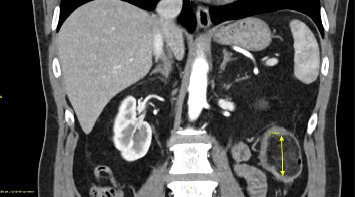

Abstract Image